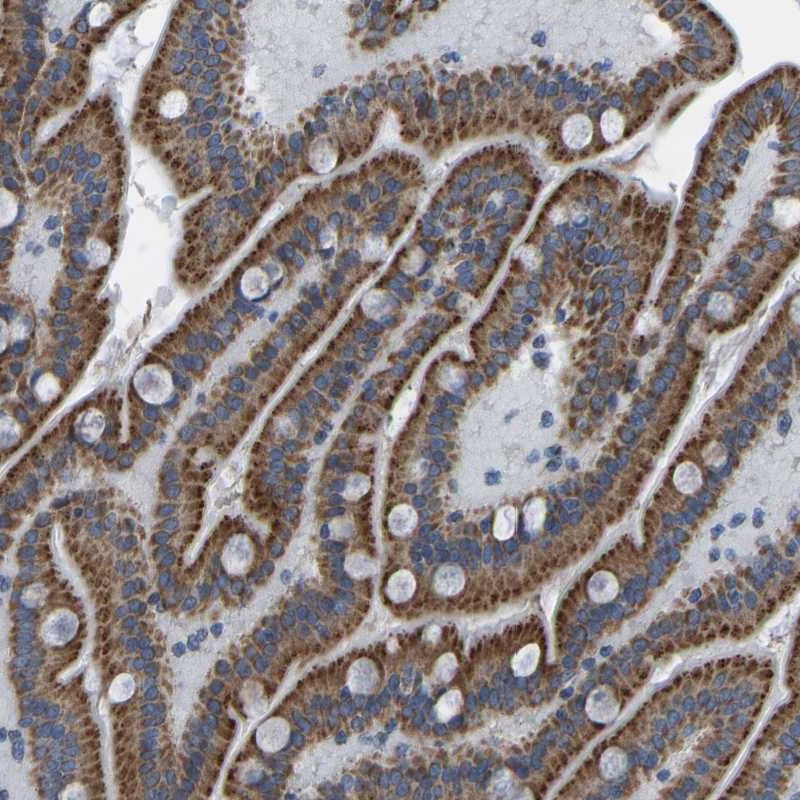

Immunohistochemical staining of human duodenum shows strong cytoplasmic positivity in granular pattern in glandular cells.